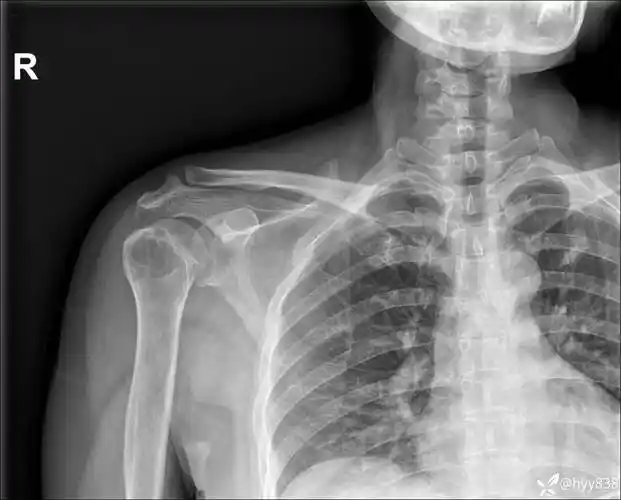

胸部影像挑战# 年轻女性肩痛 1 月,咳嗽 4 天,入院体温 39.9°c.

中年女性,发现右肩关节占位2天.有特征,有细节---(有结果)